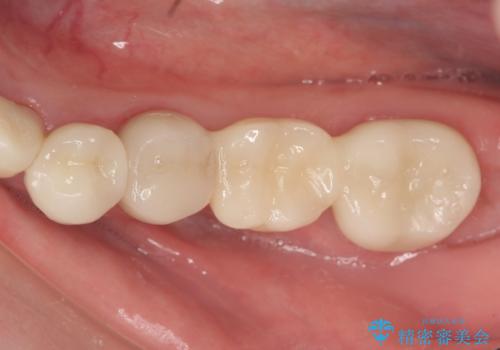

下顎は左側 4 番目から右側 4 番目までの 8 歯と左下 567 ブリッジをオールセラミッククラウンで補綴し、右下67の銀歯はセラミックインレーによる修復を行いました。

当院のセラミックインレーはemaxという強度と審美性に優れた材料を使用しています。

またプレス方式でインレーを製作しているため、削り出しで製作するCADCAMより優れた適合性も持ち合わせており、虫歯が再発しにくい修復物です。

今回用いたオールセラミッククラウンはジルコニアフレームという白い素材の上にセラミックを盛っているため、審美性が非常に高いのが特徴です。

また、ジルコニアは人工ダイヤモンドの材料にも使われているほど高い強度を持っており、そのためオールセラミッククラウンは審美性だけでなく、奥歯やブリッジの補綴も可能とするクラウンです。